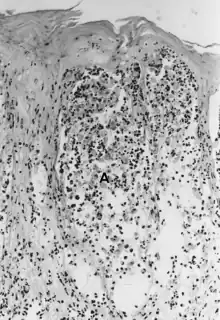

| Foot-and-mouth disease - acantholysis in a sample of a skin vesicle: Necrosis of the stratum spinosum can be observed, and keratinocytes floating in the vesicular fluid (spongiosa). | |

Acantholysis is the loss of intercellular connections, such as desmosomes, resulting in loss of cohesion between keratinocytes,[1] seen in diseases such as pemphigus vulgaris.[2] It is absent in bullous pemphigoid, making it useful for differential diagnosis.

This histological feature is also seen in herpes simplex infections (HSV 1 and 2) and varicella zoster infections (chicken pox and shingles).